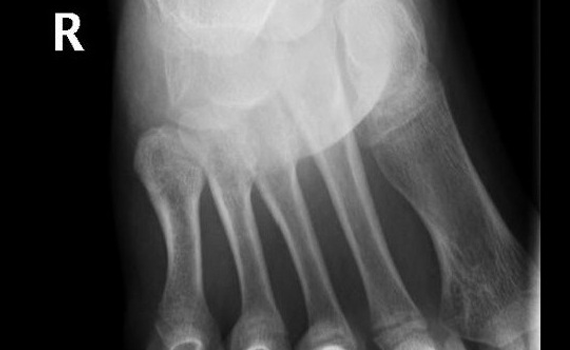

Hallazgo radiográfico tras movimiento anómalo del pie